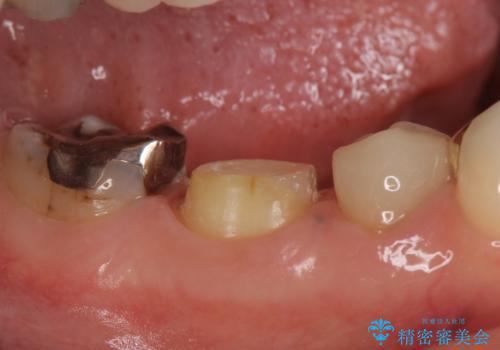

- 右下奥の歯茎がたまに腫れて膿が出るので診て欲しいといらっしゃった方の症例です。

診査の結果右下6の歯の神経が死んでいたため根管治療を行い、オールセラミッククラウンによる補綴を行いました。